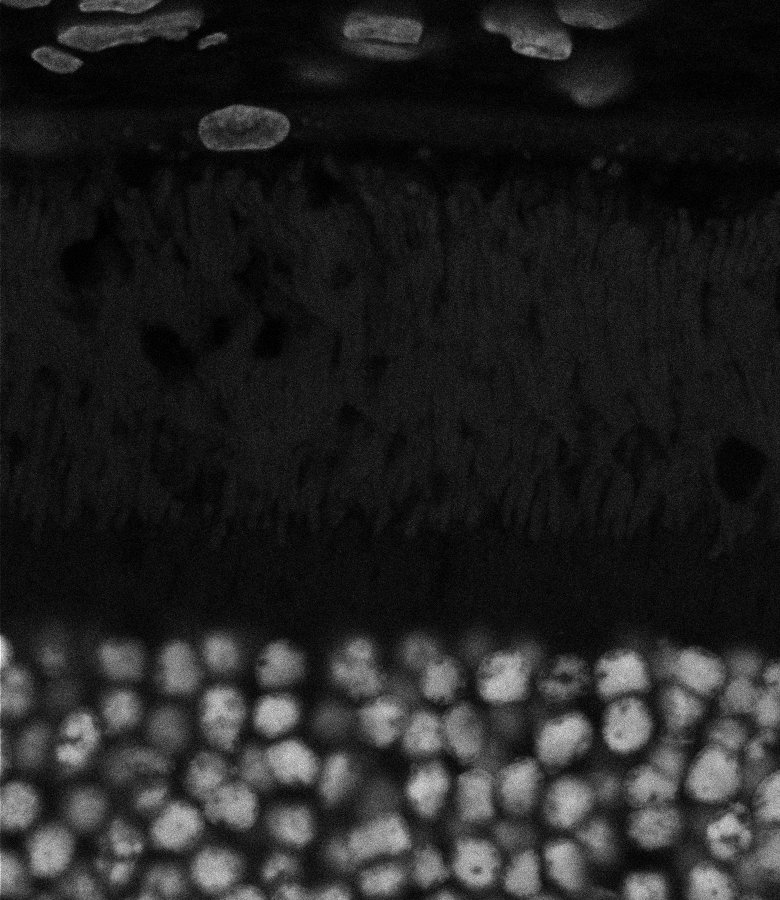

Tubulin

Overview 2

Tubulin - Bip

Tubulin - Nuc

Overview 4